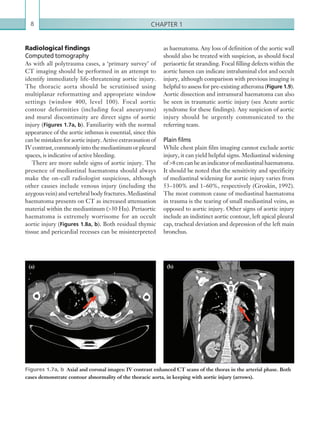

As with all polytrauma cases, a ‘primary survey’ of

CT imaging should be performed in an attempt to

identify immediately life-threatening aortic injury.

The thoracic aorta should be scrutinised using

multiplanar reformatting and appropriate window

settings (window 400, level 100). Focal aortic

contour deformities (including focal aneurysms)

and mural discontinuity are direct signs of aortic

injury (Figures 1.7a, b). Familiarity with the normal

appearance of the aortic isthmus is essential, since this

canbemistakenforaorticinjury.Activeextravasationof

IVcontrast,commonlyintothemediastinumorpleural

spaces, is indicative of active bleeding.

Figures 1.7a, b  Axial and coronal images: IV contrast enhanced CT scans of the thorax in the arterial phase. Both

cases demonstrate contour abnormality of the thoracic aorta, in keeping with aortic injury (arrows).

(a) (b)